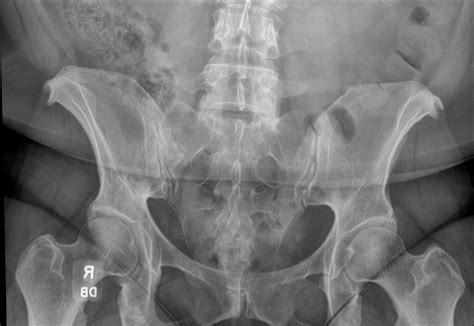

Diagnostic imaging plays a crucial role in evaluating the Alae of Sacrum and the surrounding structures. Various imaging modalities are used to assess the anatomy and function of the sacral alae, including:

• X-rays: Provide a basic overview of the bone structure and can help identify fractures or dislocations.

• Sacroiliac Joint Dysfunction: This condition can cause pain in the lower back, buttocks, and hips, often radiating down the legs. It is often diagnosed through a combination of clinical examination and imaging studies.

Diagnosing these conditions often involves a combination of clinical examination, imaging studies, and laboratory tests. Treatment options vary depending on the underlying cause and severity of the condition.